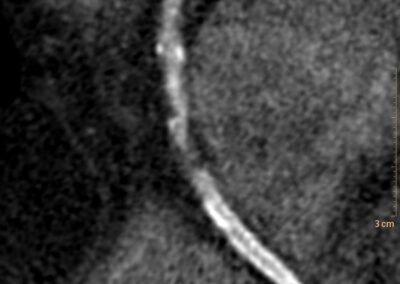

στεφανιογραφία στον αξονικό τομογράφο.

Τρισδιάστατη και δισδιάστατη απεικόνιση των στεφανιαίων αγγείων όπου διακρίνεται σημαντικότατη στένωση της δεξιάς στεφανιαίας αρτηρίας λίγο πριν το προϋπάρχον stent, το οποίο απεικονίζεται φυσιολογικά βατό